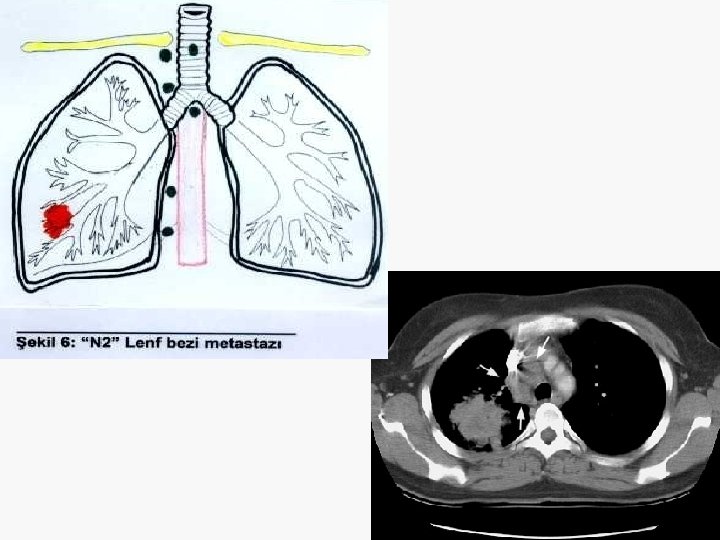

Evreleme EVRE 0 : Tis N 0 M 0 EVRE IA : T 1 N 0 M 0 EVRE IB : T 2 N 0 M 0 EVRE IIA : T 1 N 1 M 0 EVRE IIB : T 2 N 1 M 0 T 3 N 0 M 0 EVRE IIIA : T 1 -3 N 2 M 0 T 3 N 1 M 0 EVRE IIIB : T 4 N M 0 T N 3 M 0 EVRE IV : T N M 1

Non-invaziv evreleme (1) Toraks BT’de kısa çapı 1 cm’den büyük LAM’lar anlamlı kabul edilir ama bu metastatik anlamına gelmez. Toraks MR – Süperior sulkus tümörlerinin evrelemesinde kullanılmalı – Mediasten ya da toraks duvarı invaz. değerlendirmek için önerilmez.

İnvaziv evreleme (1) BT’de LAP pozitif operabl olgularda mediastinoskopi zorunludur. – Servikal mediastinoskopi ile 2 R, 2 L, 4 R, 4 L, 7 (anterior) ve 1. ile 3. istasyonlara ulaşılabilir. – 5 ve 6 numara için genişletilmiş mediastinoskopi ya da torakoskopi gerekir. – 7 (posterior), 8, 9 numaralar için torakoskopi gerekir. – TTİİA, TBİİA, mediastinoskopiye alternatiftir, ancak negatif sonuçlar metastazı dışlamaz.